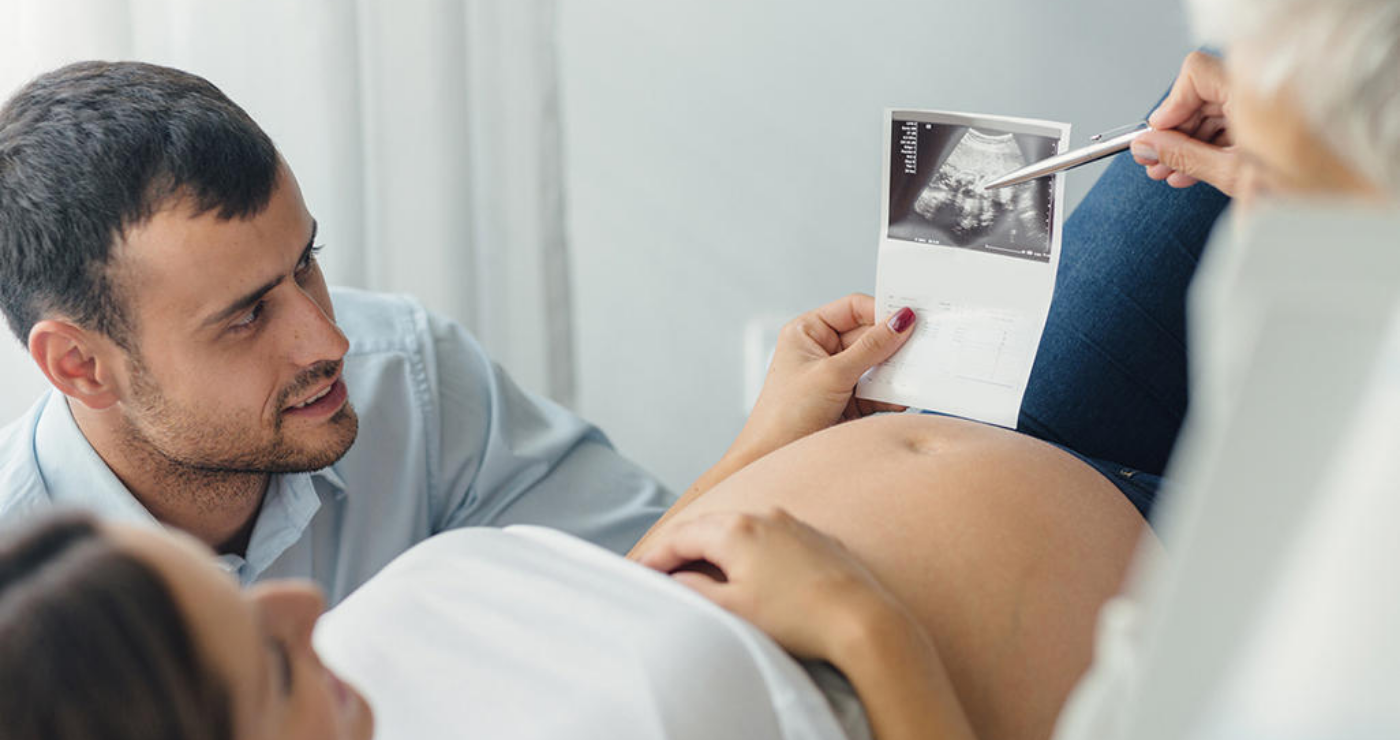

Ecografía del corazón fetal en 4D

Ocho de cada mil bebes nace con algún defecto cardíaco congénito. Estas anomalías se producen por un desarrollo anormal del corazón durante el embarazo y pueden consistir en defectos de sus paredes o válvulas, o de los vasos sanguíneos que entran o salen de él.

En un embarazo normal o de bajo riesgo se recomienda realizarse tres ecografías, una por trimestre. La primera entre las semanas 11 y 14, la segunda entre la 18 y la 22 y la tercera entre la 32 y la 36. Descubre para qué sirve cada una de ellas.